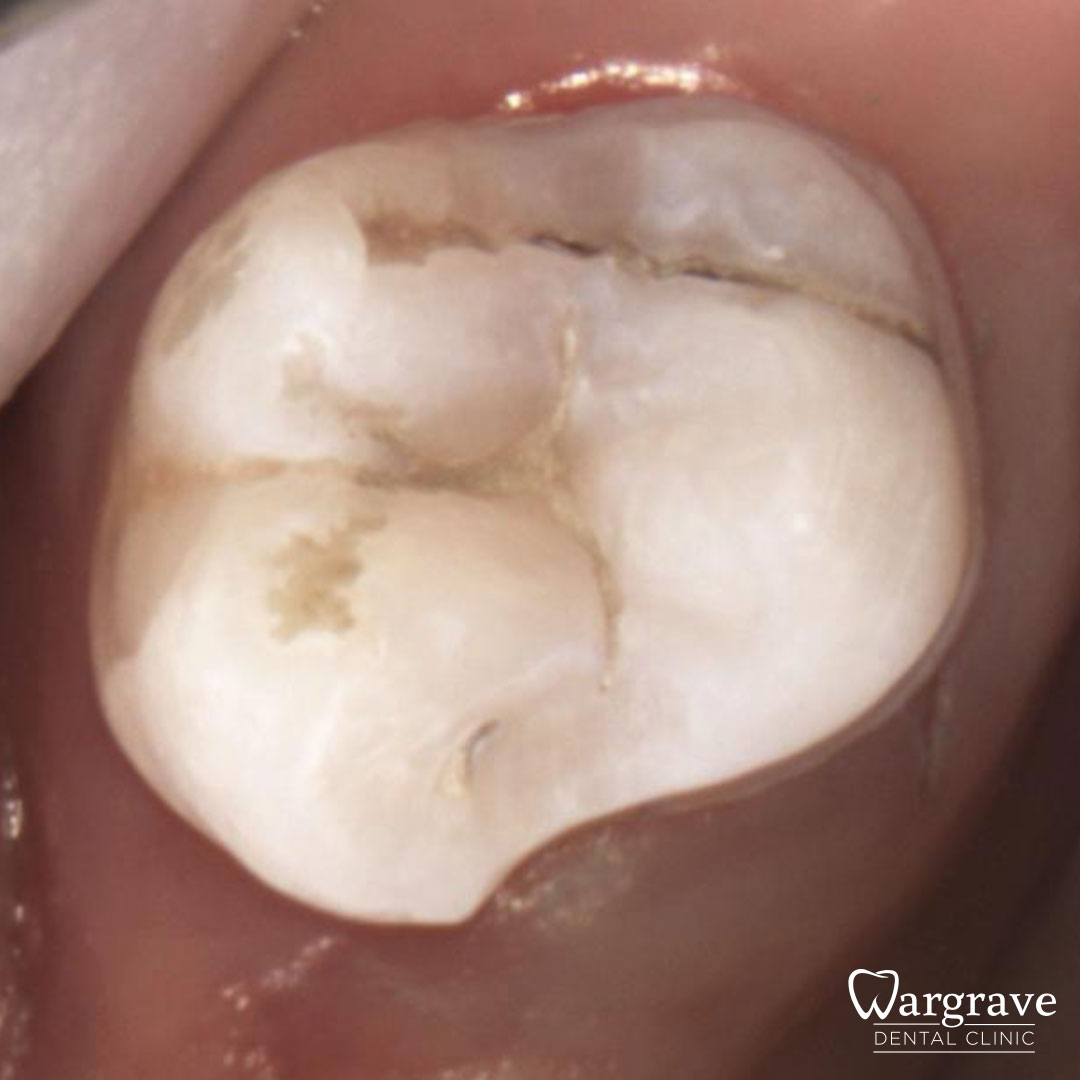

Healthy Smiles These are more advanced examples of different treatments available.All cases shown were carried out by Dr R Khurana unless otherwise stated. Immediate implants Anterior Mandible Bone Regeneration Anterior Mandibular Implant Bridge Maxillary Anterior Implant Bridge Implant stabilised ‘Life Like’ replacement dentures Implant Bridge after 10-years with zero bone loss Implant examples including ZBLC concepts Adhesive Bridge solution for a missing premolar Multidisciplinary care Orthodontics, Replacement veneers and composite bonding Adhesive Bridge solution for missing central incisors Replacement crown, Veneer and Composite Bonding Replacement Crowns and Veneer Injection Moulding using Composite Resin Equilibration Tooth Whitening to treat Developmental Discolouration